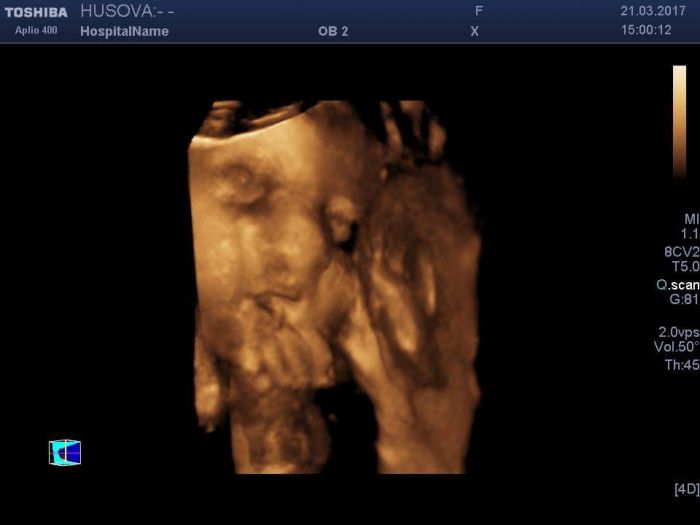

Tak jsem opravdu ráda že s tou únavou nejsem sama!!! Asi je to normální. Jinak dneska jsem byla na 3d ultrazvuku tak taky přikládám foto

Lenik... to je krasny miminko :) projde to jen me nebo to vypada jako kdyu neco povida jak ma tu pusinku pootevreno :)